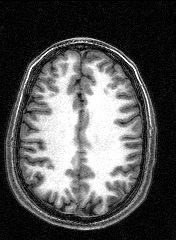

The last session involved several MRI and fMRI scans while completing tasks in the noisy environment of the scanner. Thanks to a friend who worked at the Institute, I was able to secure a copy of the raw data and an application to turn it into images, some of which are displayed here.

The images to the right are virtual 'slices', taken horizontally, starting from the top and working down. Cerebrospinal fluid is dark, the white matter appears light.